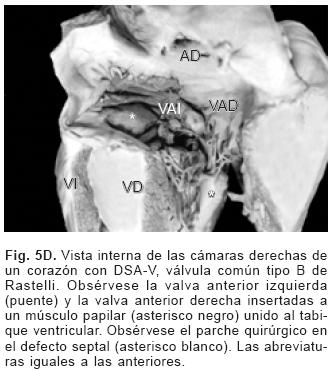

De los sesenta y cinco corazones con válvula común en veinticinco se determinaron los tipos de la clasificación de Rastelli que fueron los siguientes: en once (44%) las valvas anterosuperiores derecha e izquierda se insertaron a través de sus cuerdas tendinosas sobre la cresta del tabique ventricular y la CIV se ubicó en los espacios intercordales (tipo A de Rastelli) (Figs. 1A y 5A). En un espécimen las valvas anterosu–periores izquierda (valva puente) y derecha se insertaron sobre la cara derecha del tabique ventricular por debajo de su cresta (Fig. 5B) y en otro dicha inserción se hizo en la parte superior del cuerpo de la trabécula septomarginal (Fig. 5C). En ocho corazones (32%) la inserción de esas valvas se estableció en un músculo papilar situado en la unión del tabique ventricular con la pared libre del ventrículo derecho y la valva anterosuperior izquierda pasó como puente por encima de la CIV (tipo B de Rastelli) (Figs. 1B y 5D) y en seis corazones (24%) la inserción de las valvas anterosuperior izquierda (valva puente) y derecha se insertaron en un músculo papilar de la pared libre del ventrículo derecho y esta valva se ubicó por encima de la CIV (tipo C de Rastelli) (Figs. 1C y 5E). En los cuarenta corazones restantes no fue posible determinar los tipos de Rastelli debido a que treinta y tres de ellos presentaron doble entrada ventricular (Fig. 6A) dos tuvieron modificaciones anatómicas generadas por la cirugía y cinco por presentar mutilaciones realizadas durante la necropsia. Los cinco especímenes con dos válvulas separadas tuvieron estructura trifoliada dentro de la unión A–V común (Figs. 3B y 6B); la válvula A–V izquierda mostró una valva lateral y dos septales anterior y posterior unidas a la cresta del tabique ventricular, lo que obliteró la CIV (Fig. 6C). La válvula A–V derecha mostró una valva septal displásica, una anterior y una posterior (Figs. 3B y 6B).